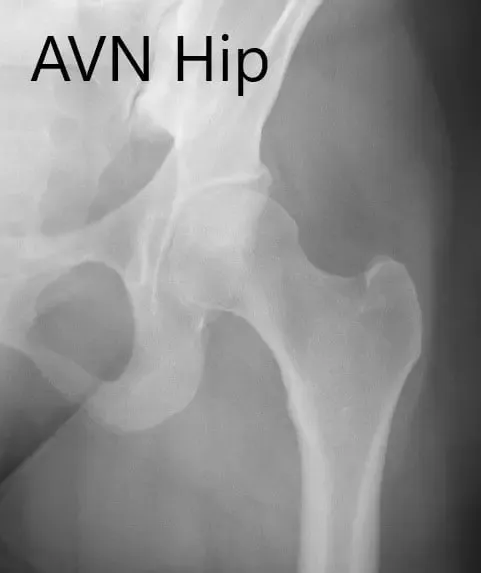

Anteroposterior view of the left hip showing pre-collapse avascular necrosis of the left hip.

The patient had Ficat & Arlet stage 2A AVN of the left hip. The patient was educated about the possibility of progression of avascular necrosis and collapse of the left hip.